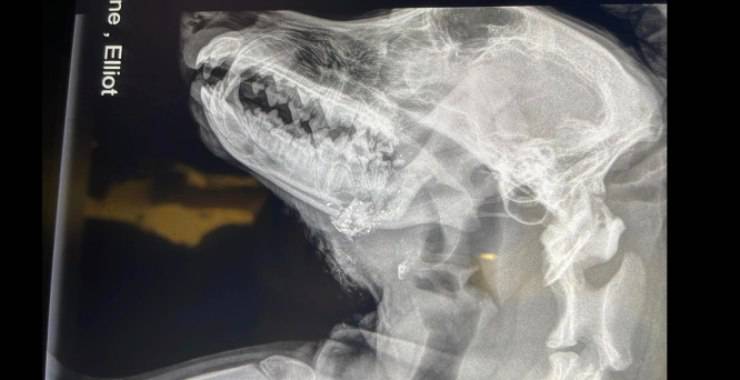

One by One Animal Advocates, un’associazione no-profit con sede a Huntington, è stata contattata da diverse persone per la situazione del povero Elliott. Il cucciolo, infatti, è stato trovato colpito alla testa da un proiettile che fortunatamente è uscito sotto la mascella. Secondo le prime ricostruzioni il colpo è partito intenzionalmente.

“Ci dispiace pensare questo, ma sembra che sia stato intenzionale perché gli è stato sparato attraverso la parte superiore della testa ed è uscito alla base della mascella“, ha riferito Heather Aulick, presidente di One by One. “Non sembra che stesse semplicemente correndo nel bosco e si sia ferito in un incidente“. Il cucciolo è stato trasportato e operato d’urgenza, dopo una serie di radiografie, le immagini hanno mostrato i frammenti di metallo o di proiettili nella sua testa, quindi l’intervento era urgente. Il dolore che deve aver patito, inoltre, era molto forte.